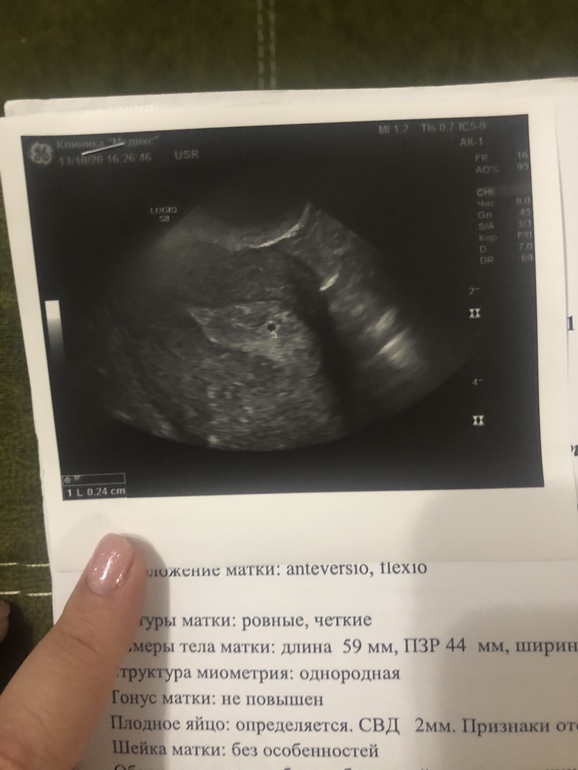

Всем привет! Девочки, посмотрите узи, пожалуйста. Первый день последних месячных был 7 сентября, закончились месячные 12 сентября. Сейчас задержка 8 дней, тесты полосатые, цифровой на выходных показывал 2-3 недели. Сделала вчера узи, плодное яйцо нашли, 2 мм. Маленькое для моего срока, да? Готовится к худшему?

Ничего не болит. Грудь только плотная и побаливает. Фото узи прилагаю